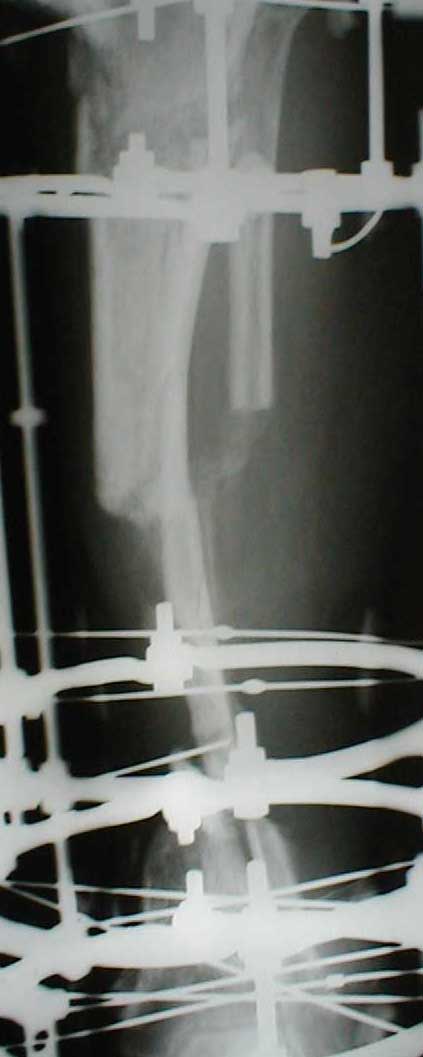

В приложении - моё наблюдение (возможно, уже представлял, тогда

извините).

Нога попала в пресс.

Ко мне больной попал черз 1,5-2 года после травмы и нескольких

операций с синегнойной инфекцией на всю голень. Меня пригласили на консультацию

насчет ампутации.

Лечил я его месяцев 8.

Малоберцовка полностью перестроилась, нога опороспособна.

При ходьбе на дальние расстояния пользуется тростью.

Осталась трофическая язва, периодически закрывается.

Клинические снимки где-то есть, но не очень качественные.

Один из вариантов.